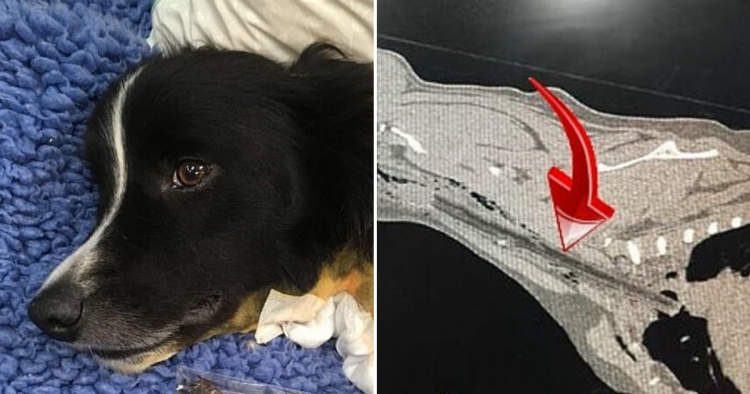

A two-year-old Border Collie named Dash was taken to the ARH as his owners were worried sick about him.

Vets immediately realized that the pooch had accidentally swallowed a stick and shared images of it on Facebook. The photos show how far the stick had been stuck down the dog’s throat.

“After they all got back home from the park his owners noticed he would no longer eat and seemed a bit ‘upset’. So Dash’s very worried family took him to our team at ARH Baulkham Hills on the Saturday evening.

“Our Emergency team immediately examined Dash and determined he was painful around the mouth and cervical region… basically the back of the neck!”

“After being sedated, our team discovered he had a penetrating wound to the right side of the base of his tongue and they could feel a hard foreign body (believed to be a large stick) along the peri-laryngeal area to the thoracic inlet.